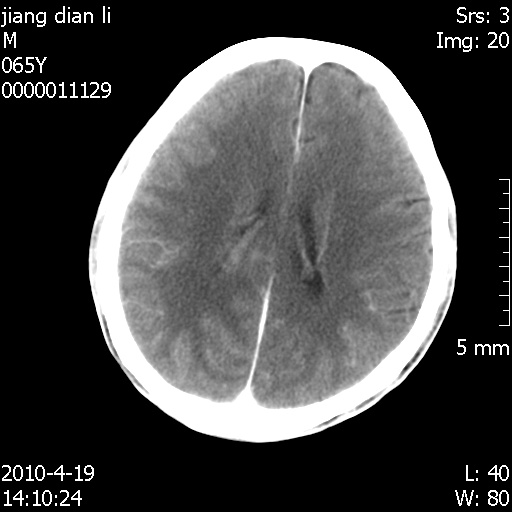

老年男性,突发左下肢无力1天,其余有价值的检查都没有。平扫ct值大约60hu,增强后ct值没什么改变,请大家讨论一下这个病例是什么?说明诊断理由。

左小脑、右大脑顶叶多发圆形高密度病灶,其周环状低密度影。考虑多发脑出血。隔期观察。